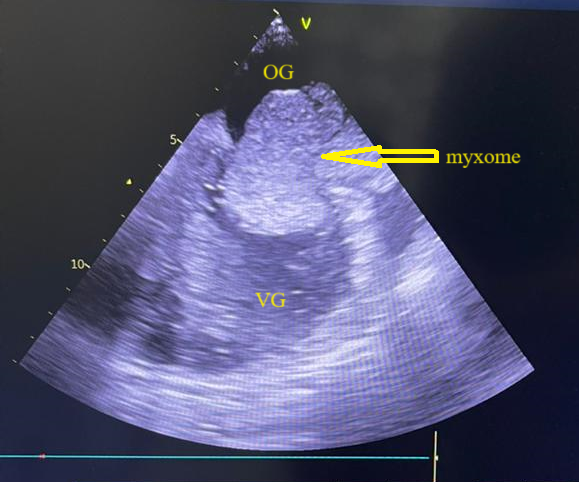

L’électrocardiogramme s’inscrivait en rythme sinusal régulier avec une fréquence cardiaque à 74bpm. L’échocardiographie transthoracique a mis en évidence une volumineuse masse intra-atriale gauche mesurant 57mm x 42mm appendue au septum inter atrial, avec dilatation de l’oreillette gauche et de l’anneau mitral associée à une insuffisance mitrale sévère grade 4/4. Le diagnostic retenu était un probable myxome de l’oreillette gauche compliqué d’insuffisance mitrale sévère. Les caractéristiques de cette masse ont été confirmées à l’échographie cardiaque transœsophagienne (figure 1). La fonction systolique du ventricule gauche était préservée avec une dysfonction diastolique grade 2. Les pressions de remplissage du ventricule gauche étaient normales. Le bilan biologique n’avait noté aucune anomalie.

Figure 1 : Echocardiographie transoesophagienne en bi dimensionnelle incidence bicave montrant un myxome de l’oreillette gauche appendu au septum inter atrial (Cas clinique n°1). OG= oreillette gauche ; OD= oreillette droite